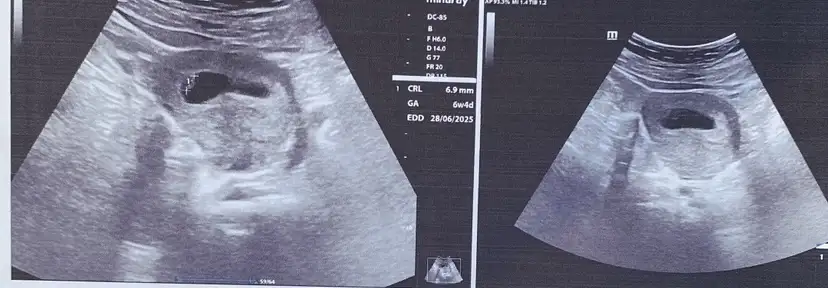

Merhaba kızlar bugün ikili test yaptırdım bebek çok hareketliydi maşallah o yüzden cinsiyet tahmini yapılamadı aşırı merakta ediyorum tahmin yapabilecek var mı 🫠

Eklentiler

• 1000023071.webp

1000023071.webp

28,7 KB · Görüntüleme: 122

Kaç haftalıkken yapıldı canım ikili taraman

Nub kısmı belirgin değil ama kız gibi hissettim

Nub teorisi yanıltıyor ben ına göre erkek diye düşünmüştüm hep kız olunca şaşırdım çok guvenmemek lazım